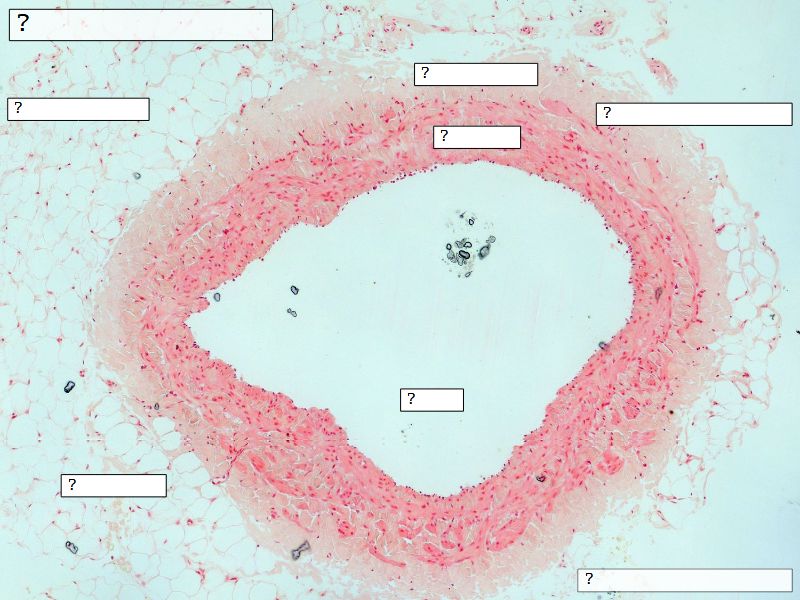

Fill in all the missing labels, and assess as you move through the slides. Answers on the down slide. It is important to do this using pen and paper, and not just glance through the images.